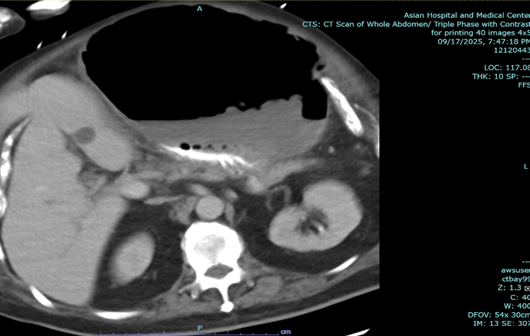

In the above latest admission, his abdominal CT Scan showed gaseous distention of stomach with ill-defined nodular thickening of posterior aspect of the body; the previously noted large lesion in stomach was not clearly demonstrated due to gaseous distended stomach.

Figure 2: a-c: September 17, 2025 Abdominal CT Scan showing previously noted large mass in stomach not clearly demonstrated due to gaseous content.

Endoscopic esophagogastroduodenoscopy plus endoscopic internal drainage using plastic stent and insertion of duodenal tube were done on 23 September 2025, repositioned to the jejunum on 29 September 2025. By x-ray (5 October 2025), a gas-filled mass is still appreciated in the upper abdomen, in the region of the stomach. The feeding tube was seen coursing within, with its tip located lateral to the mass, which may be in the distal segment of the stomach. No distinct kink was noted in this study.

The patient was readmitted for fever and anemia, and resolved accordingly. X-ray of abdomen showed unchanged gas-filled focus.

Figure 3a,b: X-ray of abdomen.